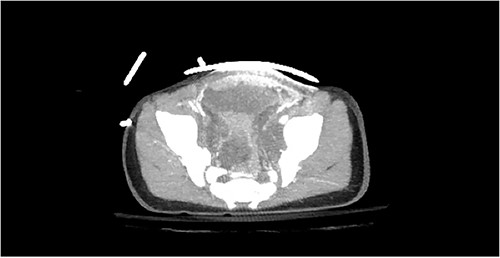

Computed tomography (CT) of the head and spine showed no other injuries. CT chest, abdomen, and pelvis showed a femoral neck fracture, grade IV liver injury, grade II splenic injury, and a fracture of the left iliac wing (Figs 1 and 2), along with a left sided bladder hematoma secondary to a pubic ramus fracture (Fig. 3). Interventional radiology was consulted to evaluate the liver and splenic injuries.